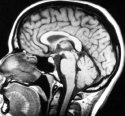

JMO and i'm no radiologist but it looks to me like her brain has pretty much liquefied in the middle. Part of the corpus callosum has been turned into a puddle and the rest looks pretty abnormal too.

Here's what a more healthy brain looks like

Correct. I'm no radiologist either, but the destruction here is so dramatic anyone can see it. The midbrain, corpus callosum, and pons are pretty much completely gone (probably necrotic and liquefied), including the lower medulla portion of the brain stem below the pons.The cerebellum appears to just be a lump or knob. And we have to remember that this is only ONE view-- there are hundreds of slices. Makes me wonder if this is the BEST view they obtained, not the worst.

Dr. Shewmon only mentions the pons briefly, almost in passing, before launching into a discussion about the remnants of cerebral cortex that remain. That seems very strange to bypass such significant portions of damage in his discussion, but we have to remember that he probably was contacted to see if he was willing to focus his comments on a very specific and narrow area of interpretation. I get the sense that he may have been recruited to be part of Dolan's team kind of late in the process. He is not required to be comprehensive or impartial in what he testifies to. (And his document is dated Oct 3. Dolan and Children's Hospital filed their memorandum and response with the court Sept. 30.)

With this much destruction, I really don't understand how a neurologist could think that it could be possible for Jahi to hear anything, or make any kind of voluntary movements. It seems very impossible, with those areas of the brain gone.

ETA: And I think we have to be forthright here. There are swaths of very critical brain tissue that are completely gone. That is more than "brain damage."